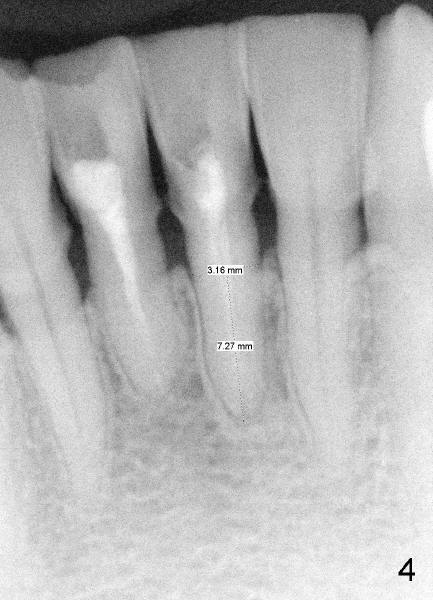

Two PAs were taken at different angulations (Fig.1,2 vs. 3,4).  The shortest M-D width of the tooth #24 is 3.16 mm (Fig.4 vs. 4.54 mm in Fig.2, probably close to the B-L width).

There is plenty of dimension in height.  What is the appropriate size of the implant?  How to handle the discrepancy of M-D and B-L widths?